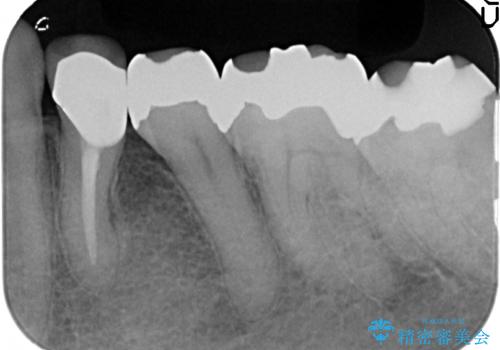

オールセラミッククラウン 疼きの治まらない歯の治療

- 他院にて左下4の根管治療を行っていたが、疼くような痛みが引かないため当院にいらっしゃった方の症例です。

左下4の再根管治療を行い症状が治まったのち、オールセラミッククラウンによる補綴を行いました。